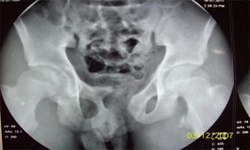

X Ray Showing Deformed Pelvis Scars of Multiple Pelvic Reconstructions

He was evaluated and investigated in detail and planned for artificial urinary sphincter. Preoperatively, micturating cystourethrogram, urodyanmic study, cystoscopy were done. The upper tracts were normal. There was no vesicoureteric reflux, stricture. Bladder capacity was 250 ml, maximum detrussor pressure was 30 cm of water and insignificant residual urine.

The upper tracts were normal and the urinary bladder had normal capacity and pressures and there was no blockage to urine flow, so he was an ideal candidate for artificial sphincter.